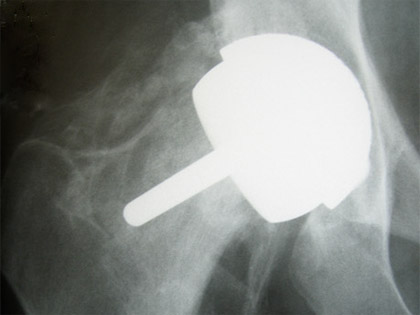

X-Ray showing standard femoral stem with large metal head articulating with metal socket.